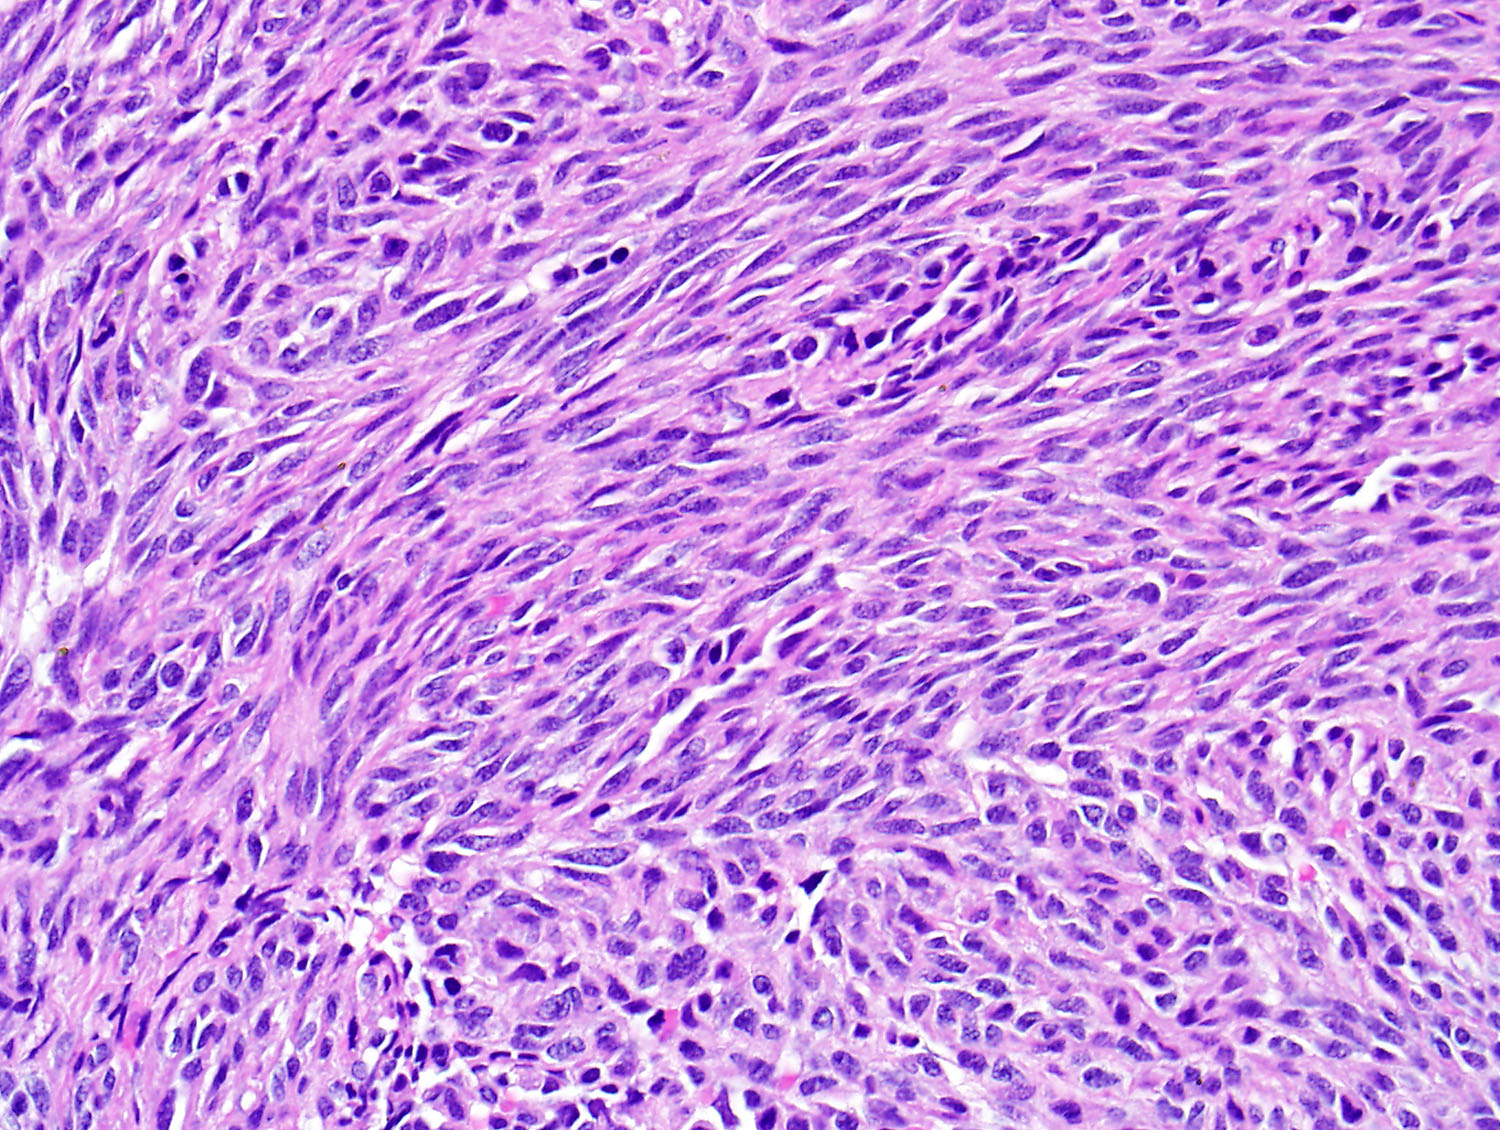

Микропрепараты: Лимфогранулематоз и Нодулярный Склероз